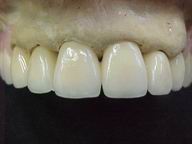

Reabilitação funcional e estética em ambas as arcadas

com próteses fixas e removíveis de encaixe de precisão.

DEPOIS